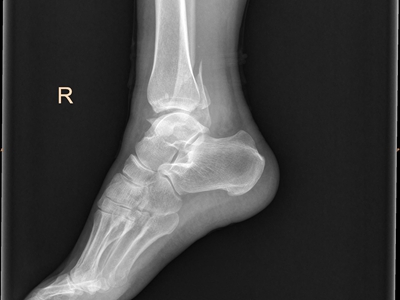

以上为骨折脚踝外侧的骨头有裂口图。

骨折发生于患者脚踝处,表现为骨头有裂口,并有一定程度的移位,局部可出现皮肤淤青、肿胀、疼痛等症状。